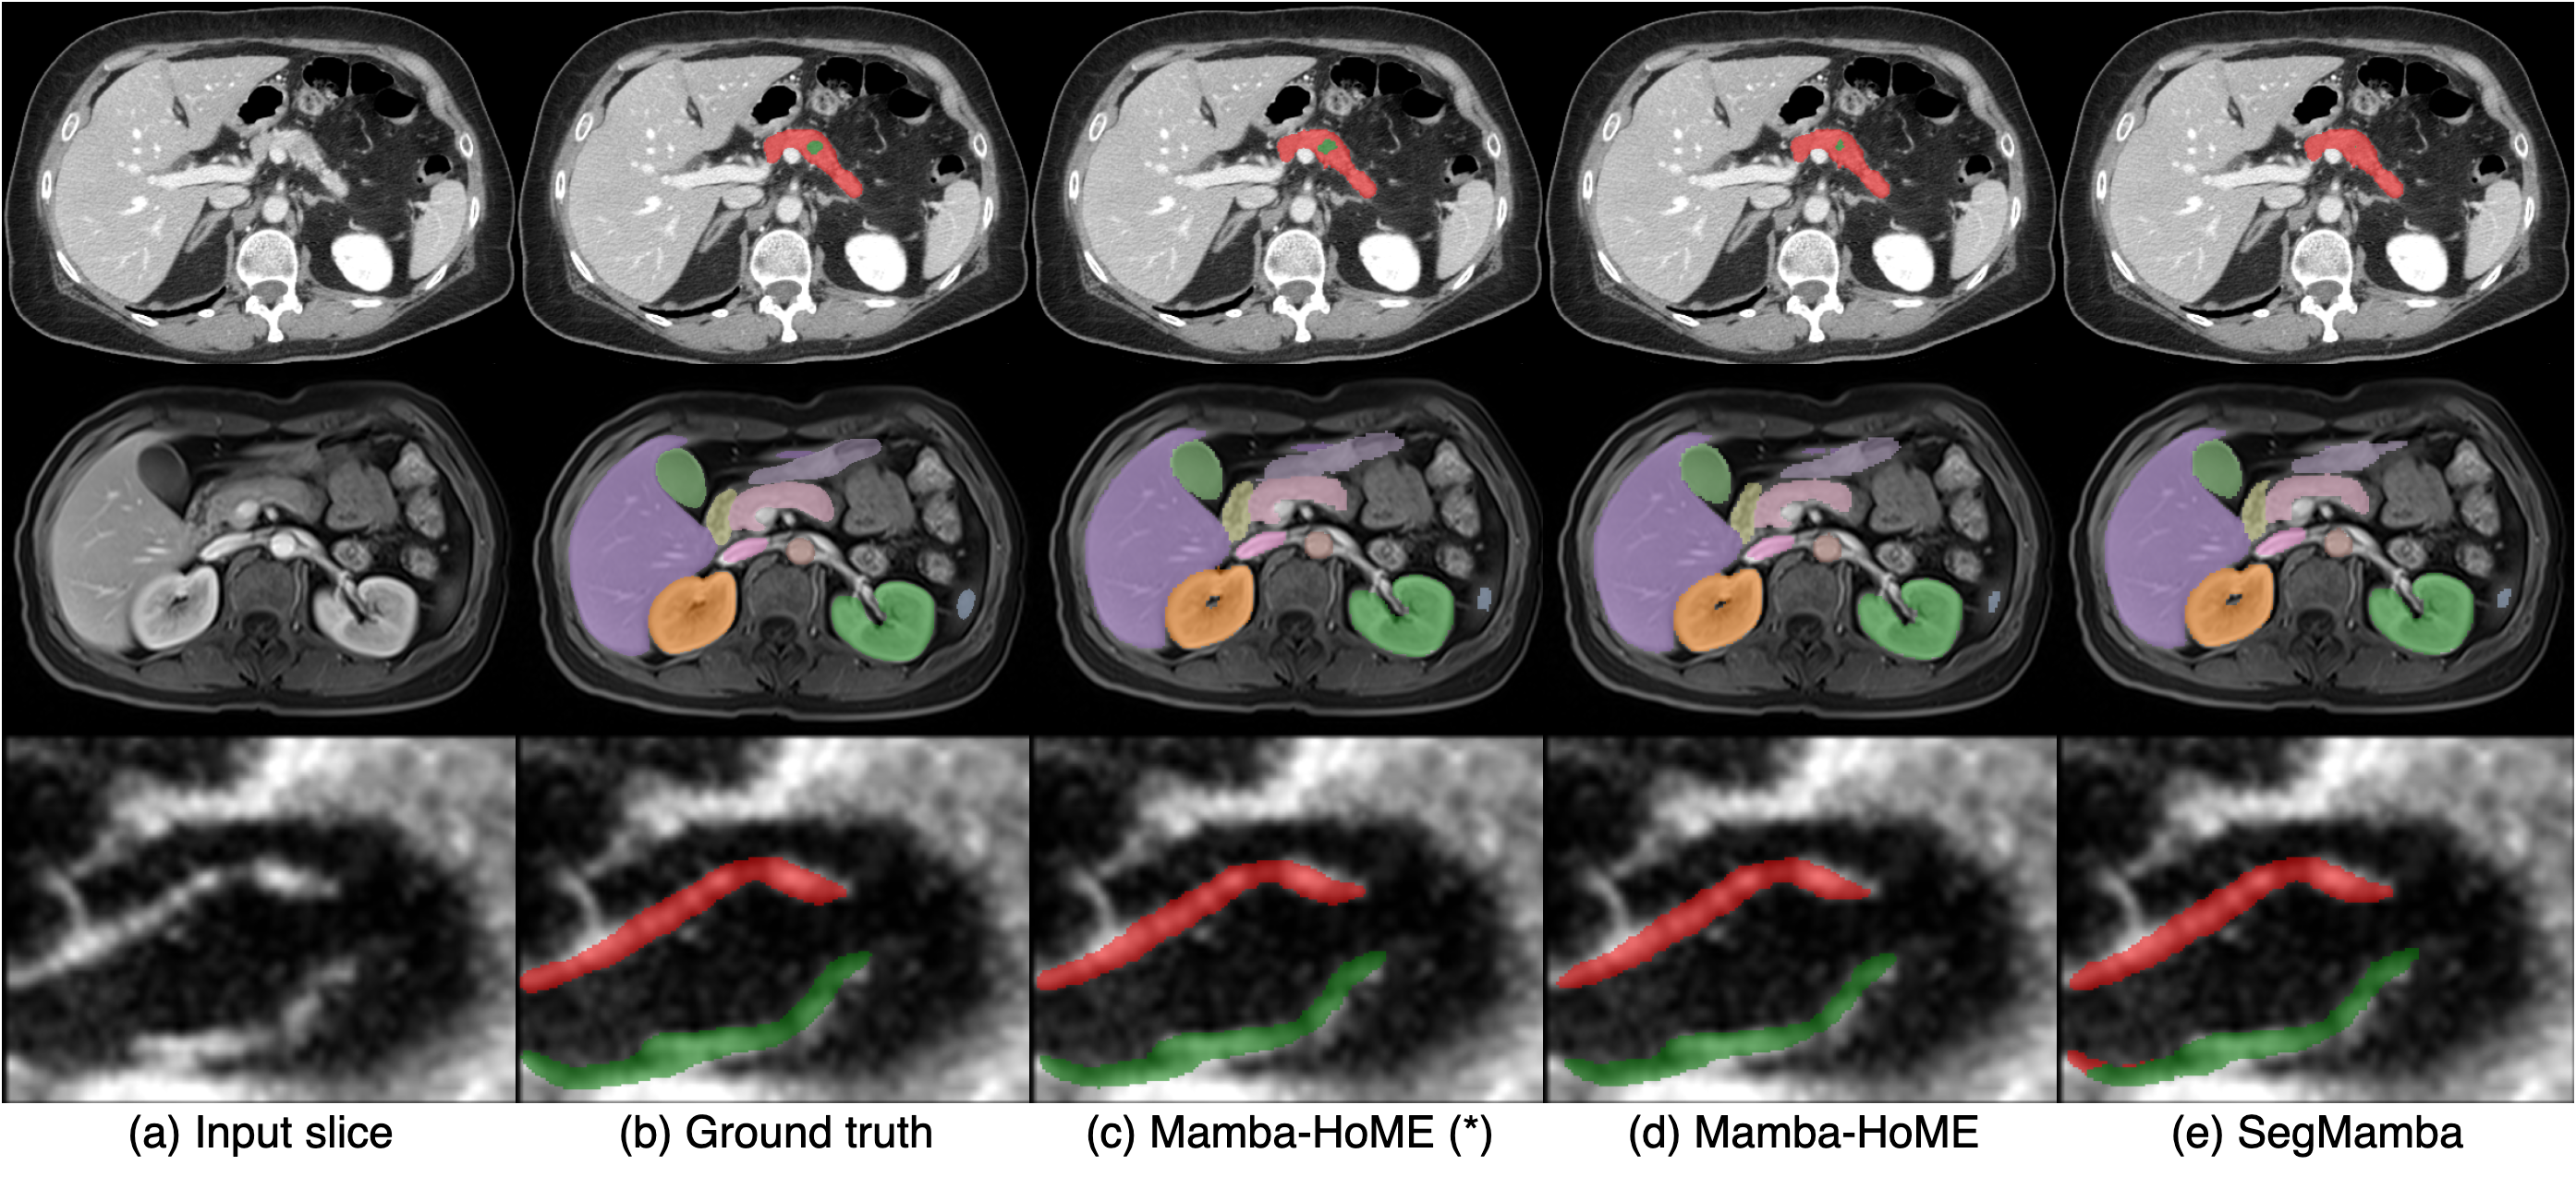

This adaptability highlights Mamba-HoME’s ability to mitigate challenges posed by variations in modality, resolution, and clinical context. Moreover, its consistently high performance across heterogeneous datasets underscores its potential for practical deployment, where robust, modality-agnostic feature representations and precise segmentation are essential for scalable, real-world medical imaging applications. As shown in Figure 3, supervised pre-training significantly improves Mamba-HoME’s performance compared to training from scratch or baseline methods, reducing artifacts and enhancing boundary segmentation for objects of varying sizes across the three primary 3D medical imaging modalities.

Figure 3: Qualitative segmentation results from top to bottom: CT, MRI, and 3D US. From left to right, each column shows the input slice, ground truth, our proposed pre-trained Mamba-HoME, Mamba-HoME trained from scratch, and the baseline SegMamba.